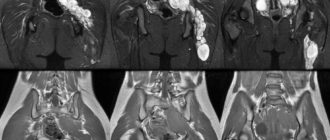

Мрт малого таза в Балашихе — 5000 руб Основными наиболее эффективными инструментальными методами диагностики